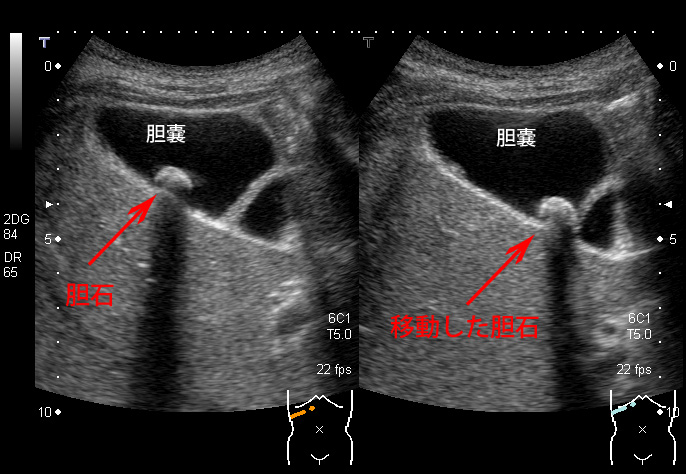

• 胆嚢炎の超音波画像診断のすべて

超音波スキャンは、医師が胆嚢炎を診断するために使用する主な検査の 1 つです。スキャン検査により、医師はこの症状の原因となる胆石の存在を発見できる場合があります。

医師が胆嚢炎の可能性があると判断した場合、超音波検査を受けることがあります。

胆嚢の超音波検査は、胆嚢疾患の兆候を最初に検査するのに最適な画像検査です。臨床医は胆石炎症が存在するかどうかを確認できます。

超音波検査では、胆嚢炎に関連する多くの要因を見つけることができます。これらには次のものが含まれます。

• 胆石

超音波は、胆嚢開口部の胆石を特定し、マーフィー徴候を観察するのに最も正確です。結果として、これらは超音波検査者が胆嚢炎を診断するために探す主な所見となります。

胆嚢炎の超音波所見は何ですか?

胆嚢炎がある場合、超音波検査で胆嚢の開口部に胆石の存在が示されることがよくあります。また、胆嚢が腫れているかどうか、または胆嚢の周囲に体液が蓄積しているかどうかも示される場合があります。